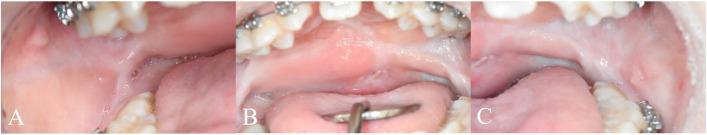

A 14-year-old female with a bilateral complete cleft lip and palate underwent primary cheiloplasty at 3 months and palatorrhaphy at 9 months of age. Despite 10 years of speech therapy and 4 years of speech aid use, hypernasality persisted. To address this, palatal lengthening was performed using bilateral buccinator myomucosal flaps combined with buccal fat flaps. At 1 month postoperatively, partial necrosis of the buccal fat grafts was observed but healed without further complications. At 8 months postoperatively, soft palate elongation exceeding 1 cm was achieved, and nasometric assessments demonstrated nasality reductions of 25.5 percentage points for high vowels (/i/, /wi/) and 19.5 percentage points at the sentence level. In the consonant accuracy evaluation, the patient's word-level accuracy increased from 72.09% preoperatively to 88.37% at 6 months postoperatively. These objective improvements correlated with subjective reports of improved speech and reduced vocal effort.

一名14岁双侧完全性唇腭裂女性患者,3个月时接受了一期唇裂修复术,9个月时接受了腭裂修复术。尽管进行了10年的言语治疗和4年的助音器使用,鼻音过重问题仍然存在。为解决此问题,采用双侧颊肌黏膜瓣联合颊脂瓣进行腭部延长术。术后1个月,观察到颊脂瓣部分坏死,但愈合良好,未出现进一步并发症。术后8个月,软腭延长超过1厘米,鼻音测量评估显示高元音(/i/,/wi/)鼻音降低25.5个百分点,句子水平鼻音降低19.5个百分点。在辅音准确性评估中,患者单词水平的准确性从术前的72.09%提高到术后6个月的88.37%。这些客观改善与言语改善和发声努力减少的主观报告相关。